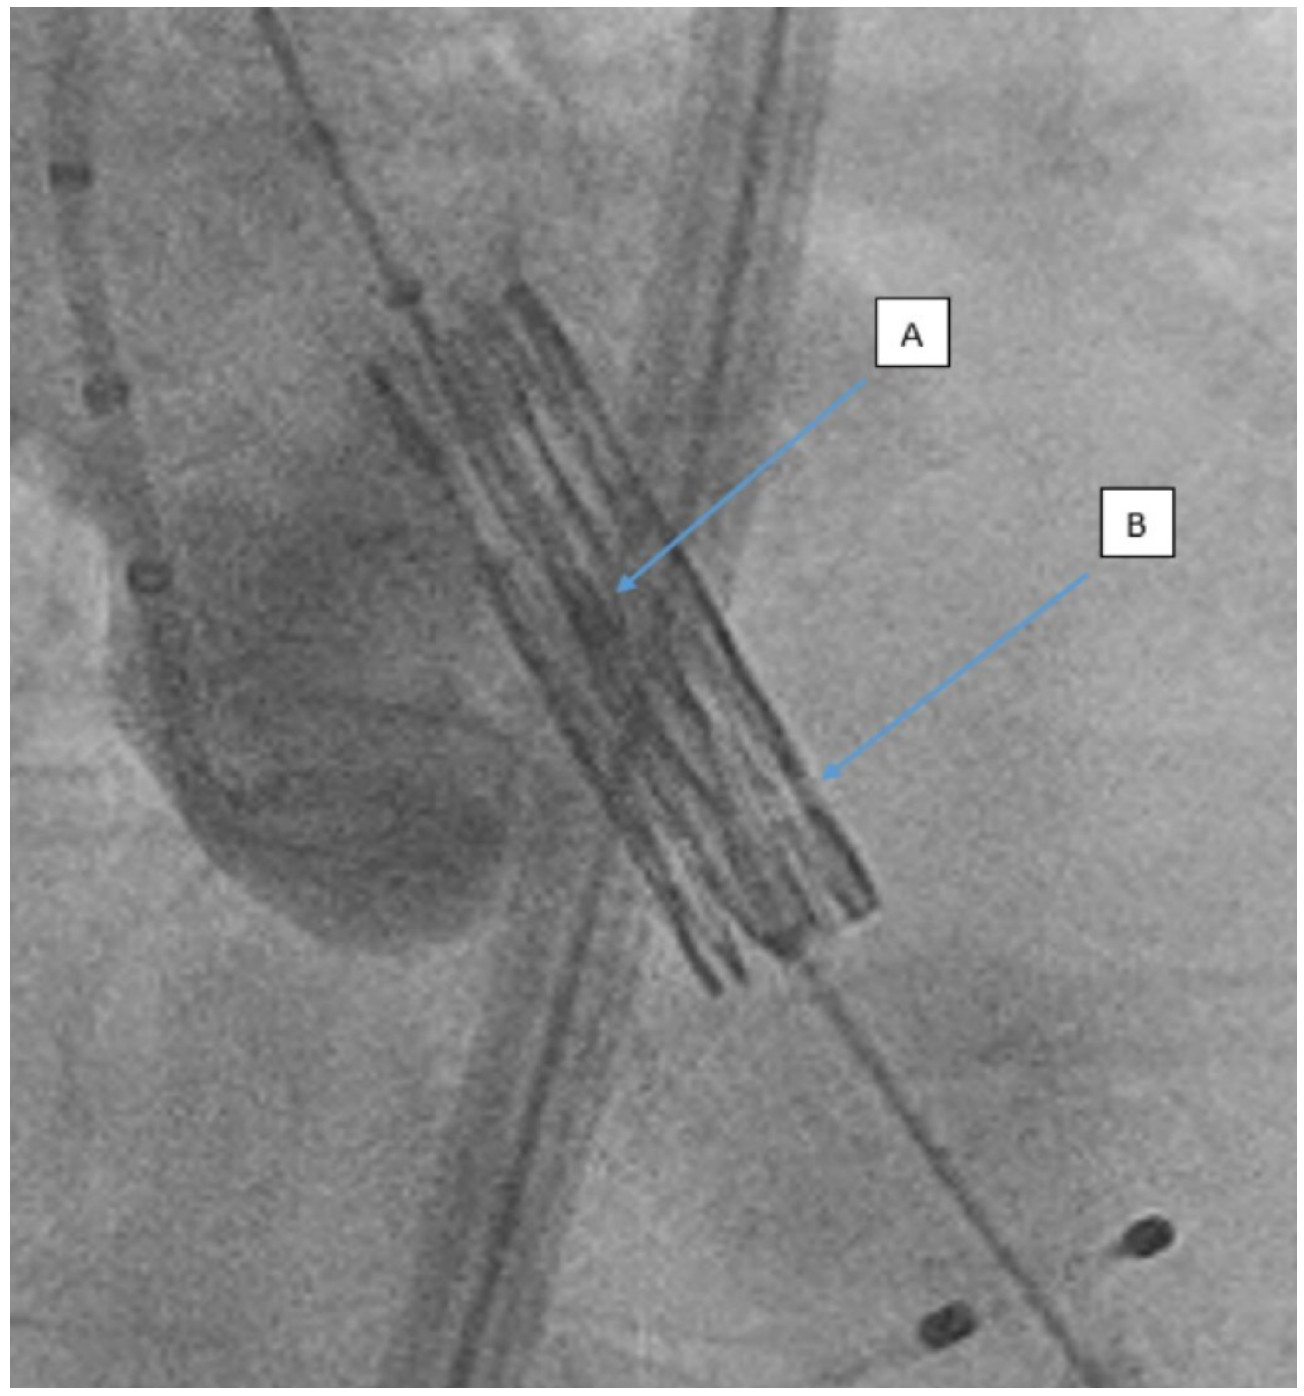

Gilbert Tang, MD: It’s a great topic and is actually quite controversial. “Lucent line” refers to a radiolucent (“lucent”) line on the Sapien 3 valve (Edwards Lifesciences). Someone posted on Twitter that they saw a space on the bottom part of the Sapien 3, used it as a reference to deploy the valve, and found that it can help achieve a higher implant to avoid a pacemaker. I did not know what the lucent line was all about until this discussion on Twitter, and people started asking, "Do you see it every time? Is it reproducible?" No one seemed to be able to give a clear answer.

Subsequently, there were two papers published, one by Cleveland Clinic, using lucent lines of reference in a right anterior oblique (RAO) caudal projection to demonstrate that the pacemaker rate is lower using that technique. Then, the Vancouver group with Janar Sathananthan also showed that with the cusp overlap view, you could achieve a higher implant and reduce the pacemaker rate. However, Edwards recommends that the Sapien 3 be deployed in a coplanar view or a three-cusp view, not in a cusp overlap view or an RAO caudal view.

We wanted to determine the percentage of time that the lucent line is actually visible when using the manufacturer-recommended view because no one had yet looked into that. Also, if you do see the lucent line, what is the percentage of time that there is actually a coaxial deployment of the Sapien 3, meaning that you see the lucent line because there is no parallax on the valve and you don't see any parallax on the valve either after deployment.

In our study looking at over 1100 cases, we found that the lucent line was only visible about 64% of the time. Among those cases where the lucent line was visible, only in slightly over two-thirds was a coaxial deployment actually achieved. In the remaining one-third, a noncoaxial deployment was achieved. For those cases where the lucent line was not visible, almost 99% of the time, there was not a coaxial deployment.

Our conclusion was that first, the lucent line is not visible 100% of the time when the Sapien 3 is deployed in a coplanar manufacturer-recommended view. Second, we looked at the implant depth of the 3 most common groups we found (lucent line visible + coaxial implant; lucent line visible + noncoaxial implant, and no lucent line visibility + noncoaxial implant). If you have a visible lucent line and a coaxial implant, the implant depth ended up statistically deeper than the other two scenarios. We weren't doing lucent line-based deployment at the time; in this study, we were only looking at whether the lucent line was visible or not during valve deployment. The lucent line doesn't really help, because it is not always visible during valve deployment — almost 35% of the time, you have to use another method to visualize and plan for the implant depth. We also found that whether the Sapien 3 valve is coaxial or noncoaxial after deployment made no difference, at least for the in-hospital rate, for paravalvular leak, pacemaker, or vascular complications. There is no difference in hemodynamic performance whether or not the valve is coaxial after deployment.